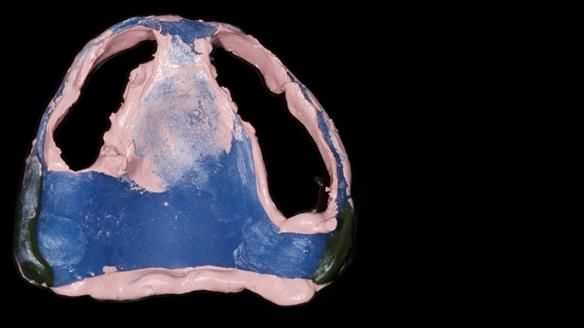

We provided her with an immediate upper denture (Mk 1), followed by a definitive metal-based upper denture (Mk 2). A lower removable partial denture was discussed, to be made only if needed once the upper treatment was complete. However, at review, this wasn’t necessary — Adnana had excellent neuromuscular control and function, even with a shortened dental arch (SDA).

Rowan, Sam Hesketh and Chris Hesketh provided the stunning technical work. I am very lucky to have them.